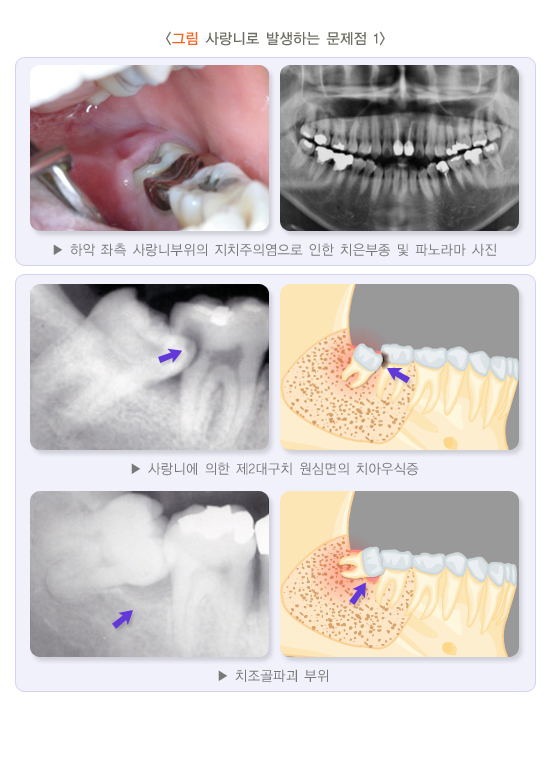

(5) 제2대구치(두번째 큰어금니) 원심면(뒷부분) 치아 병변

사랑니가 앞쪽 방향으로 기울어 매복되면 앞 어금니 뒤쪽 면에 음식물이 쉽게 끼어 치아우식증이 생기기 쉽고, 진행되면 통증이 생길 수 있습니다. 어금니 치아우식증이 진행되면 사랑니 발치 시 약해진 치아가 부서지기도 합니다. 통증 감소와 치아 손상 방지를 위해 발치 전 또는 발치 후 어금니의 치료가 필요할 수 있습니다. 대개 근관(신경)치료를 포함하여 보존 및 보철치료를 하게 됩니다. 사랑니가 옆으로 누워있으면 앞 어금니의 뿌리가 흡수되는 경우가 있습니다. 사랑니에 의해 이미 손상된 치아는 사랑니의 발치 전후로 정밀한 검사가 필요합니다. 손상이 매우 심하면 앞의 어금니를 뽑기도 합니다. 치아가 시리거나 아프거나 다른 증상이 있다면 이미 앞의 어금니가 손상되었을 가능성이 높습니다.